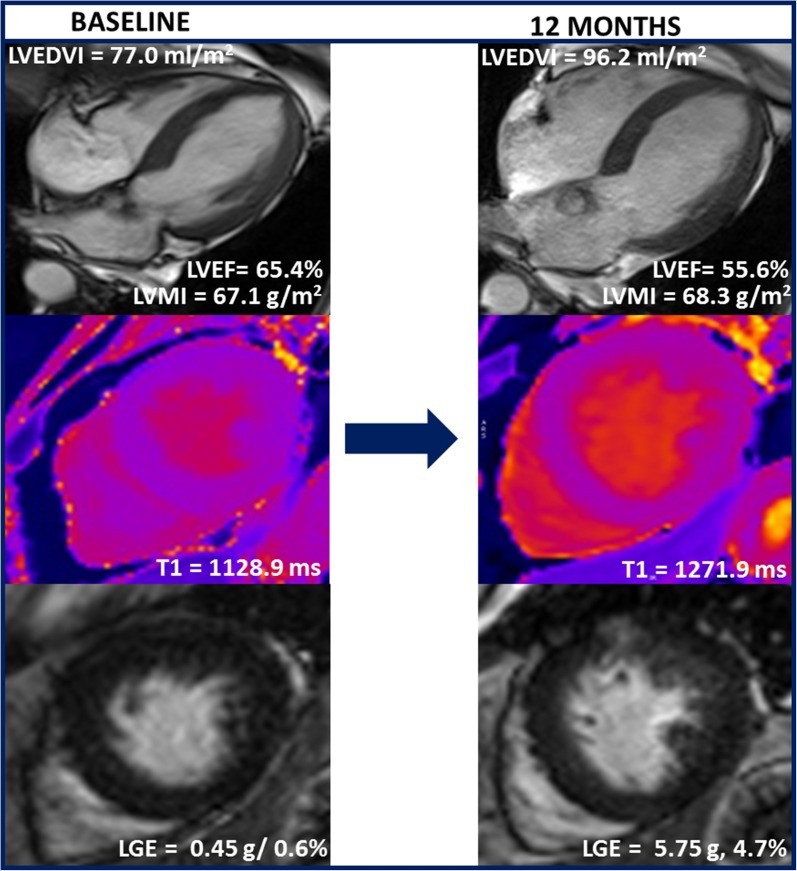

Watchful waiting in asymptomatic patients with severe aortic stenosis and preserved LVEF is currently recommended. However, the pressure overload imposed to the LV by the stenotic valve can lead to irreversible myocardial fibrosis which has shown to portend poor prognosis even after aortic valve intervention. Singh et alref. 13 investigated whether adverse LV remodeling progresses in the short term in 44 asymptomatic patients with moderate-to-severe aortic stenosis (83.4% male, indexed aortic valve area 0.54 ± 0.15 cm2/m2) included in the PRIMID-AS (PRognostic Importance of MIcrovascular Dysfunction in Aortic Stenosis) study. Cardiovascular magnetic resonance (CMR) imaging was performed at baseline and 12-month follow-up. The authors observed a significant increase in indexed LV end-diastolic volume (from 90.7 ± 22.0 to 94.5 ± 23.1, P = 0.007) and indexed LA volume (from 52.9 ± 11.3 58.6 ± 13.6, P < 0.001), reduction in LVEF (from 57.9 ± 4.6% to 55.6 ± 4.1%, P = 0.001) and impairment in LV diastolic function (longitudinal diastolic strain rate from 1.06 ± 0.24 s−1 0.99±0.24 s−1, P = 0.026) despite no change in the indexed aortic valve area. In addition, there was a significant reduction in rest and stress myocardial blood flows and increases in myocardial fibrosis both on native T1 mapping and late gadolinium enhancement (LGE) imaging (Figure 3). These findings demonstrate unequivocal progression of adverse cardiac remodeling in asymptomatic moderate-severe aortic stenosis in 12 months, emphasizing the need of improved patient risk-stratification tools and potential need for earlier intervention.